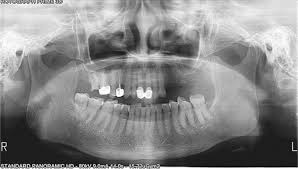

Qua một trường hợp bệnh nhân cụ thể đến khám tại Khoa Răng: Bệnh nhân nữ, 62 tuổi đến khám với lý do đau tức nửa mặt bên trái. Khai thác tiền sử và bệnh sử, bệnh nhân đã nhổ răng 2.6 rất lâu, không còn nhớ rõ nhổ răng hết hay còn chân răng; khám trên lâm sàng, sống hàm vùng lợi R2.6 liền lợi tốt; không có biểu hiện viêm nhiễm; không có tê bì, mất cảm giác da. Bệnh nhân được chụp phim Panorama thường qui để kiểm tra thấy xoang hàm T có hình ảnh viêm, nghi ngờ do còn sót chân răng trong xoang nhưng không rõ. Bệnh nhân được chụp tiếp Cone Beam CT, qua các lớp cắt đã thấy rõ hình ảnh có một phần thân răng nằm trong xoang hàm T; từ đó kết hợp với Trang chủ Hubet1122 uy tín lập kế hoạch cụ thể Hubet8888 lì xì hội viên mới viêm xoang lấy bỏ chân răng trong xoang hàm.

Hình 1: Phim Panorama không rõ có tổn thương